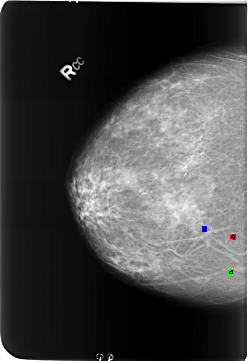

B_3223_1.RIGHT_CC

FILE: B_3223_1.RIGHT_CC.OVERLAY

TOTAL_ABNORMALITIES 3

ABNORMALITY 1

LESION_TYPE CALCIFICATION TYPE LUCENT_CENTER DISTRIBUTION N/A

ASSESSMENT 2

SUBTLETY 3

PATHOLOGY BENIGN_WITHOUT_CALLBACK

ABNORMALITY 2

ABNORMALITY 3